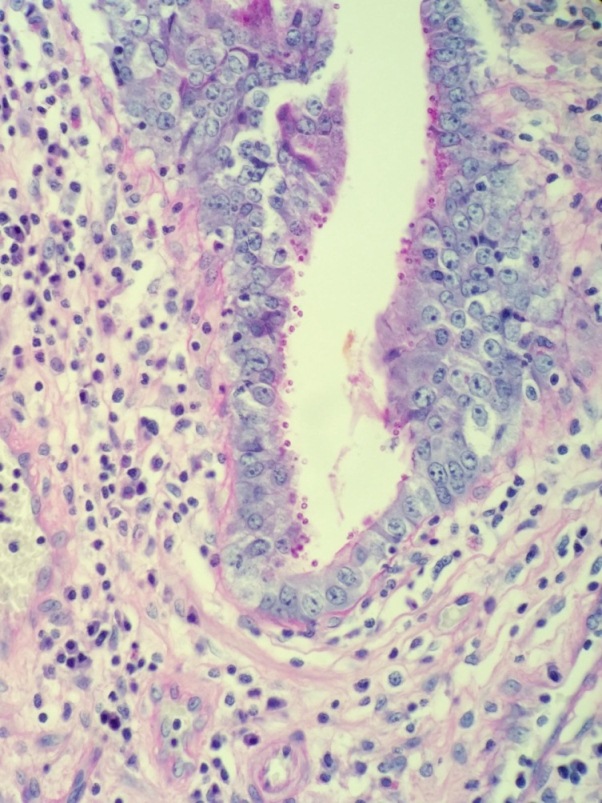

In tissues and body fluids, Coccidioides is identified as round, thick-walled spherules (10-80µm) containing multiple endospores (2-5µm). When cultured at both 25°C and 37°C, Coccidioides forms wooly, white-grey colonies which may turn brown as they mature. The coarse hyphae are hyaline and septate with alternating thick-walled, barrel-shaped arthroconidia and empty cells. Although colonies usually form within three to five days, the distinctive arthroconidia may take up to 2 weeks to fully mature. Due to this delayed maturation, Coccidioides is often initially misidentified as its non-pathogenic look-a-like Malbranchea. Confirmatory testing by PCR may be performed on both bodily fluids and paraffin embedded tissue.